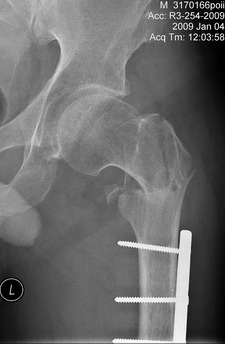

Р-гр шейки

Теперь ситуация более ясная. Оптимальным тут, очевидно, было бы малоинвазивное удаление пластины и закрытый интрамедуллярный остеосинтез длинной гаммой или другим проксимальным гвоздем. Это не только обеспечило бы надежную фиксацию всех проблемных отделов бедра, но и позволило бы немедленную полную нагрузку.

Другие варианты менее привлекательны, хотя в итоге могли бы привести к успеху. Но ценой большей травматичности, длительности лечения, неудобств, трудоемкости и с бОльшими рисками неприятностей. Вариантов очень много - скелетное вытяжение, тазобедренная повязка, остеосинтез DHS или другой пластиной с угловой стабильностью, остеосинтез таким или другим аппаратом...